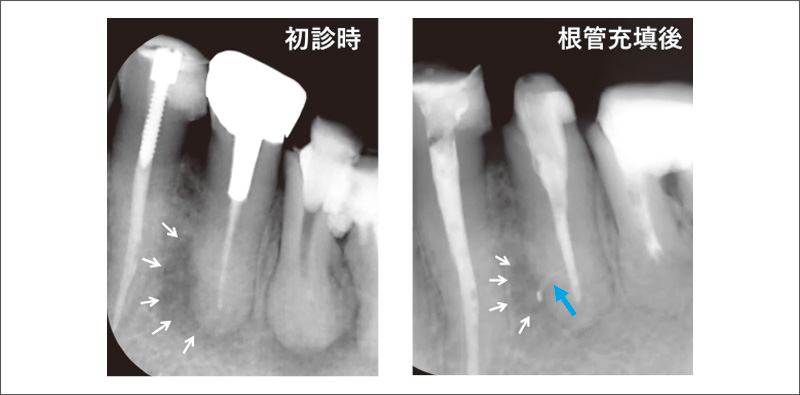

![[写真] 管間側枝への根管充填(69歳女性)](/academic/dentalmagazine/wp-content/uploads/sites/2/2025/09/194-1_photo11.jpg)

図11 管間側枝への根管充填(69歳女性)

ML根管からの充填で、MB根管にもシーラーが浸入(青矢印)し、管間側枝も容易に封鎖された。 -

![[写真] 側枝への根管充填(59歳男性)](/academic/dentalmagazine/wp-content/uploads/sites/2/2025/09/194-1_photo12.jpg)

図12 側枝への根管充填(59歳男性)

側枝へのシーラーの浸入(青矢印)がみられ、近心側面の骨欠損も縮小(白矢印)した。 -